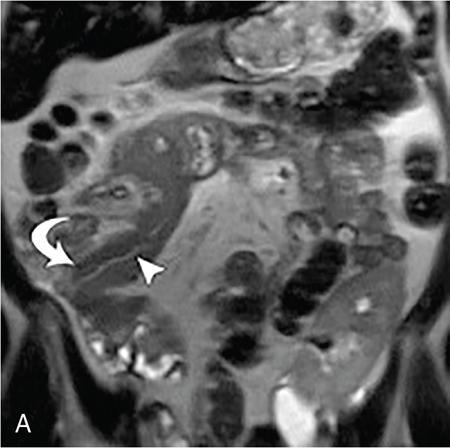

Kajal Patel, L. Murali Krishna Pancreatic transplantation is currently the only effective treatment for type 1 diabetes mellitus (93% of cases) allowing long-term glycaemic control without exogenous insulin injections. Additionally, it also counteracts the complications of diabetes mellitus, including diabetic neuropathy, retinopathy, vasculopathy and end-stage renal failure. The standard procedure is transplantation of a whole-organ cadaveric pancreas but less-invasive approaches such as islet cell transplantation are in development. Simultaneous pancreas–kidney (SPK) transplantation (78%) is done in most of the cases with same donor. In 16% cases, pancreas transplant can be done after kidney transplant also. But rarely, isolated pancreatic transplant (6%) can be done. The first pancreatic transplantation was performed in 1966 by the team of Dr. Kelly, Dr. Lillehei, Dr. Merkel, Dr. Idezuki Y and Dr. Goetz, 3 years after the first kidney transplantation. According to Scientific Registry of the United Network for Organ Sharing (UNOS) and the International Pancreas Transplant Registry (IPTR), the national 1-year patient, kidney and pancreas survival rates for recipients of an SPK transplant are 95%, 89% and 85%, respectively. Pancreas grafts have vascular and enteric connections that vary in their anatomic approach and understanding of this is critical for imaging. Imaging techniques are directed to display the pancreatic transplant arterial and venous vasculature, parenchyma and intestinal drainage pathway. Various surgical techniques have evolved over the years especially in the recent decade. Imaging of these patients should also be done based in the common surgical techniques and complications that arise of these surgeries. Though multiple modalities like ultrasonography (US), computed tomography (CT) and magnetic resonance (MR) imaging, radionuclide study and digital subtraction angiography (DSA) are available, each of them have their own advantages and limitations and usually a multimodality approach is required to diagnose the spectrum of complications. Preoperative evaluation typically considers the potential recipient’s age and ability to survive the operation. A relative contra-indication is the patient’s age (>55 years), due to the fact that the success rate is superior in younger individuals. Key components of the assessment include determining the presence of renal, cardiac, peripheral vascular, cerebro-vascular and psychiatric diseases. The pretransplant work-up consists of extensive laboratory, infectious and physiologic testing. Chest radiography is required for preoperative fitness of recipient. The extent of aorto-iliac calcification of recipients, a factor in choice of implant site, is evaluated with unenhanced CT. Donor factors such as age, sex, body mass index, cause of death, donation after cardiac death, serum creatinine and preservation time (cold ischaemia) can influence the outcome of pancreas transplantation. Usually, evaluation of donor pancreas is best done by the pancreatic transplant surgeon intraoperatively. Visual inspection of pancreas in terms of its size, texture, colour, fibrosis, fatty infiltration and its vascular supply is essential. There is very little role for preoperative imaging in the setting of deceased organ donation. The donor’s pancreas is harvested en bloc with its respective vascular support and a variable duodenal segment that contains the ampulla of Vater. The most common technique consists placing the pancreatic graft intraperitoneally in the right pelvic region with the duodenal segment facing cephalad and the renal graft in the left iliac fossa, extraperitoneally. Whole pancreatic graft transplantation can be performed with a duodenal segment; in this type of transplantation, donor’s duodenum is anastomosed with the recipient’s small bowel loop for enteric exocrine drainage and grafted portal vein is anastomosed with common iliac vein or inferior vena cava for systemic endocrine drainage (Fig. 9.20.1). Another way of restoring the endocrine drainage, grafted portal vein may be anastomosed with the recipient’s portal venous system and for exocrine drainage duodenal segment may be anastomosed with the urinary bladder. Duodenoenterostomy done by side to side anastomosis of donor’s duodenal segment to the recipient’s small bowel loop. Arterial supply is established by using the donor’s aortic patch, containing the splenic artery and the superior mesenteric artery (SMA), which is anastomosed to the recipient’s common or external iliac artery. Native pancreas of patient is left untouched in the upper abdomen. After placement of pancreatic graft by surgeon, pancreatic graft Doppler evaluation should be done intraoperatively. Intraoperative ultrasound probe is directly put on anastomotic artery and vein which show normal colour flow without evidence of thrombosis. In the case of occlusion, there is no evidence of colour flow. In the case of occlusion, surgeon does re-anastomosis of vessels once thrombi are removed. Due to its superficial location in pelvis and visualization of pulsation of vessels, visual inspection is sufficient for patency of vessels. So most of the time intra-operative Doppler study is not necessary. Postoperative imaging of pancreas transplantation is a challenge for the radiologist because of the altered surgical anatomy, identifying the pancreatic graft from adjacent structures and various postoperative complications that may arise posttransplantation. Imaging evaluation of the pancreas transplant grafts is commonly performed by a multitechnique approach. The most commonly utilized scanning techniques include US, CT and MR imaging. DSA and radionuclide study are routinely not performed nowadays. Ultrasound usually represents the first line imaging method in the assessment of the pancreatic graft, due to its portability, repeatability for ill and unstable patients in the immediate postoperative period, lack of ionizing radiation, and it provides a real-time vascular flow map which may allow detection of vascular anastomotic stenosis and reduced pancreatic graft perfusion. Its evaluation may, however, be limited due to the intraperitoneal position of the pancreas graft, in particular with the portal enteric approach with the organ in the right upper abdomen and intestinal gas overlap. Unless abnormally dilated, the duodenal component often cannot be separately evaluated by ultrasound. Additionally, ultrasound may be fundamental in guiding the percutaneous biopsy. Although the lack of an organ capsule generally results in an ill-defined appearance, the pancreatic transplant can be identified by its relatively cylindrical shape. In greyscale B-mode, the normal pancreatic graft presents homogeneous echotexture, lower than the native pancreas and the surrounding mesenteric or epiploic fatty tissue (Fig. 9.20.2). Colour and power Doppler US play a vital role in demonstrating pancreas transplant perfusion and vascular anatomy. We would also be able to visualize the Y arterial graft, graft vein, splenic artery and vein (Fig. 9.20.3A and B). Venous structures demonstrate a monophasic waveform within an anechoic lumen and velocities ranging between 10 and 60 cm/s. Normal arterial waveform exhibits a sharp systolic upstroke and a continuous diastolic flow. In the immediate postoperative period, the velocities of the arterial anastomosis may be very high as 400 cm/s due to possible postoperative oedema and/or due to kinking of the anastomosis. Usually in both the cases, the arterial anastomotic velocities gradually decrease on in follow-up. The resistive index (RI) may be of limited use to diagnose graft rejection, as the values may be as high as 0.9 and are variable throughout the gland. Due to the presence of renal capsule in a transplanted kidney, there is elevated vascular resistance when there is intrarenal oedema; however, due to the absence of capsule in the transplanted pancreas, the vascular resistance will be normal in spite of oedema secondary to pancreatitis or rejection. CT is generally required after an abnormal ultrasound or whenever the patient presents unexplained fever, abdominal pain or when abnormal laboratory data are found. Contrast-enhanced CT helps to evaluate the graft parenchyma, the enteric and vascular anastomosis and in diagnosing postoperative complications such as focal collections, vascular thrombosis or pneumoperitoneum. In noncontrast CT scan, pancreatic graft appears as a homogeneous isodense soft tissue organ. It is more difficult to differentiate between pancreatic graft and nonopacified and nondistended small bowel loop in plain/noncontrast CT scan. But you can always make out the surgical clips which are stapled on duodenal stump, which can be helpful for localization of pancreatic graft. Nonenhanced images should be acquired with the goal of locating the graft and possible early thrombus or haematoma. The protocol used should include (positive) enteric contrast that allows identification of intestinal loops adjacent to the graft and distinction from possible liquid collections (Fig. 9.20.4A). The donor’s duodenum is frequently collapsed and may fill (or not) with the given oral contrast. IV contrast material is administered infrequently, to avoid the risk of nephrotoxicity, if native renal function is impaired. About 120–150 mL of contrast medium greater than 350 mg iodine per millilitre is injected at the rate of 4–6 mL/s. Late arterial phase can be obtained with the bolus-tracking technique located in the common iliac artery (attenuation value of 150 HU) and is very useful in the assessment of parenchymal enhancement and arterial anastomosis; 50 seconds after the administration of intravenous contrast material, the portal venous phase evaluates the respective drainage and possible associated venous complications (Fig. 9.20.4B). CT images are evaluated by axial, multiplanar reformats and three-dimensional maximum intensity projection (MIP) and volume-rendered techniques. The normal pancreatic parenchyma will enhance uniformly more in the arterial phase than in the venous phase. The iliac arterial graft, peripancreatic and intrapancreatic arterial vasculature, as well as the anastomosis of the donor portal vein to the recipient iliac or superior mesenteric vein, should be delineated. Coronal reformats are the best to illustrate the intestinal anastomosis and to determine if the graft is placed inferiorly for a systemic venous drainage or superiorly for a portal venous drainage. MR is usually indicated in young patients in which cumulative radiation is an essential consideration. Contrast-enhanced MR angiography is used for evaluating the arterial and venous anatomy of pancreatic graft; however, it is difficult to access the enteric anastomosis and postoperative complications due to low spatial resolution. Also, it is a challenge to image sick patients requiring intense monitoring and those with metallic clips. An appropriate protocol includes axial T1-weighted (T1WI) (precontrast; in-phase and out-of-phase), coronal T2-weighted (T2WI) fast-spin-echo and axial T2-weighted fat-suppressed sequences. Furthermore, images after intravenous contrast administration (gadolinium-based) should be acquired in arterial and venous phases. Unenhanced MR imaging readily helps distinguish the pancreatic allograft from adjacent structures and is superior to CT without intravenous contrast material. In plain MRI of abdomen, pancreatic graft appears hyperintense as compared to liver and appears as homogenous structure on T1-weighted images. Normal pancreatic graft’s signal intensity is between that of fluid and muscle on T2-weighted images. Various pathologic process of graft pancreas is more related to increased glandular water content, so T2-weighted images are more sensitive to diagnose graft pathology (Fig. 9.20.5A). Axial and coronal images are useful in displaying pancreatic and peripancreatic graft oedema, as occurs in pancreatitis, and in characterizing peritransplant fluid collections (haematoma/seroma). The MR angiography helps to access the arterial and venous anatomy and can diagnose arterial or venous stenosis and venous thrombosis. The normal pancreas graft enhances briskly and homogeneously in the late arterial phase (Fig. 9.20.5B). Gadolinium-based contrast agents may pose the risk of nephrogenic systemic fibrosis in selected patients with advanced renal dysfunction. The normal pancreatic duct is generally not visible with US or CT but may be observed as a thin (≤3 mm) smooth line on T2W MRI.